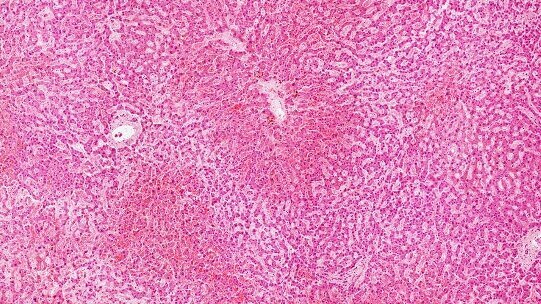

Ćelije zubne pulpe poznate su od ranije po svojstvu da se transformišu u veći broj različitih tipova ćelija, uključujući mišićne i krvne, ali ovo je prvi put da istraživači tvrde da su uspeli da proizvedu ogroman broj ćelija koje su sposobne da uskladište glikogen i da prikupe ureu – što su dve ključne funkcije jetre.

Naučnici su izjavili da, iako su potrebna dodatna istraživanja u vezi sa mogućim kancerogenim ishodom povezanim sa ovom metodom, prvi rezultati pokazuju kako proizvedene ćelije nose nizak potencijal maligne promene, što ograničava rizik od razvoja tumora nakon transplantacije.

Uobičajene metode koje se danas koriste za uzgoj hepatičkih ćelija, namenjenih humanoj transplantaciji, podrazumevaju korišćenje fetalnog seruma teladi, što je u velikoj meri ograničeno zakonskim propisima u celom svetu. Nasuprot uvreženim metodama, naučnici su tokom ovog istraživanja matične ćelije ekstrahovali iz zubne pulpe pacijenata prilikom redovnog postupka vađenja zuba. Uzorci matičnih ćelija su zatim podeljeni u dve grupe i inkubirani u vodonik-sulfidu, odnosno u drugom medijumu.